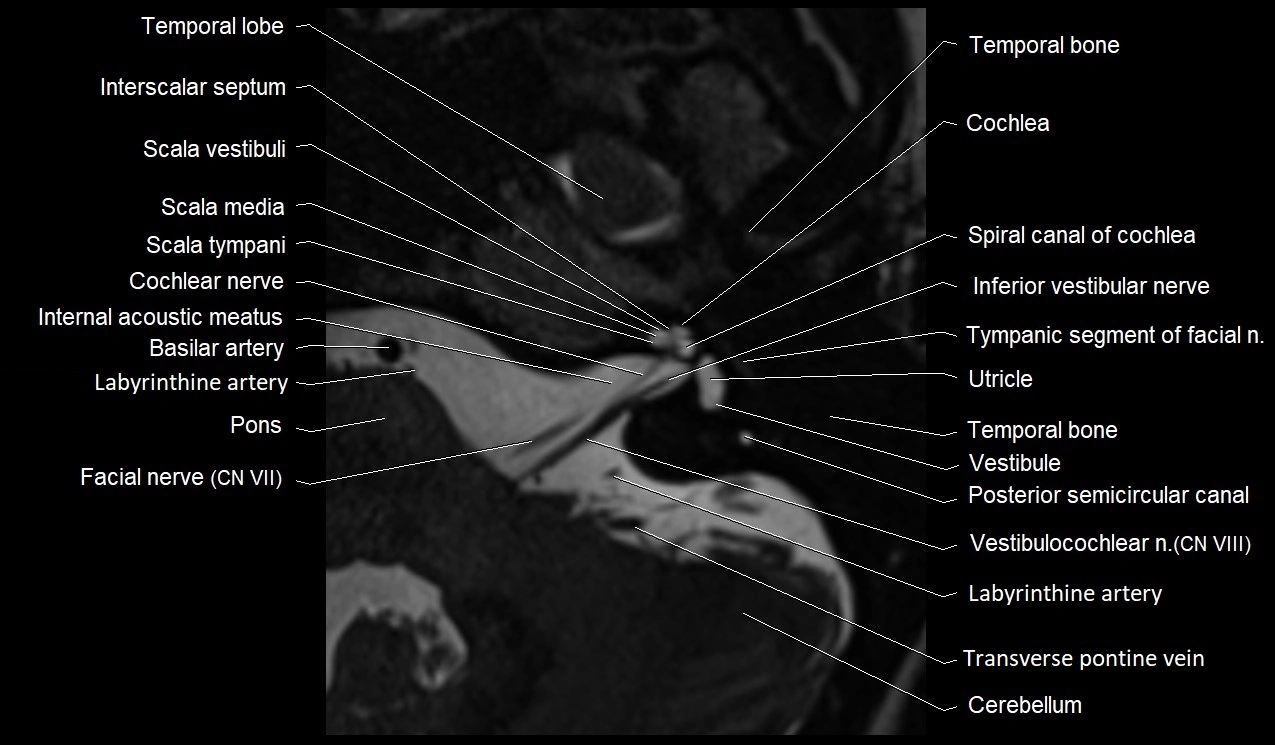

MRI images

image